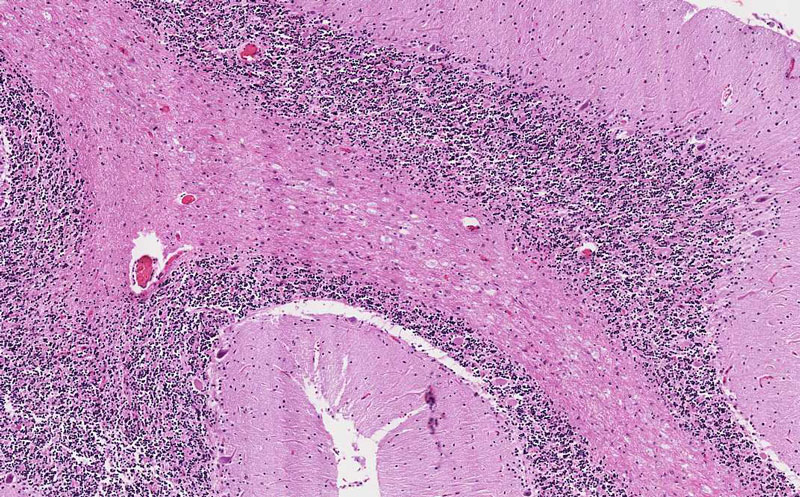

Area 2: The density of infiltrating histiocytes is much higher here. Note that there is no chronic inflammatory cell infiltration.

• On casual examination, there does not seem to be much obvious pathologic changes. On careful examination, however, there are some foamy histiocytes in the white matter (Area 1 and 2). In the superficial part of the folia, the number of histiocytes are not that numerous (Area 1) but at the base of the cerebellar folia, however, there are many histiotyces (Area 2) and it seems like that the histiocytes are slightly expanding the white matter (Area 2).